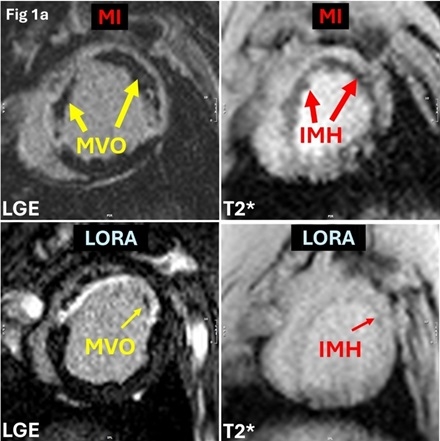

Methods: Female farm pigs (n=24; 30-35kg) underwent a 90-minute occlusion of left anterior descending artery followed by reperfusion to induce MVO. Animals were randomized into untreated MI (MI; n=12) and loratadine-treated (LORA; n=12) groups, with the latter receiving oral loratadine (10mg/day) for 5 days; after which infarcts were assessed for IMH and MVO (Figure 1a). Non-infarcted animals of the same initial weight were used as control (CTRL; n=10) group. On Day 5 post-MI, clinical 3T scanner was used to acquire cine, LGE and T2* CMR.

Results: At Day 5 post-MI, there was no significant difference in infarct size between untreated MI (25.39±6.78%LV) and LORA (22.41±3.74%LV; p=0.10) groups. End systolic volume (ESV), end diastolic volume (EDV) and peak global longitudinal strain (PLS) were not significantly different between LORA (ESV: 63.84±11.96ml; EDV: 98.52±15.62ml; PLS: -7.36±2.20) and untreated MI (ESV: 60.16±15.56ml, p=0.27; EDV: 98.51±16.24ml, p=0.50; PLS: -7.26±1.92, p=0.46). ESV and EDV in both LORA (p<0.01) and untreated MI (p<0.01) were significantly higher compared to CTRL (ESV: 31.36±6.28ml; EDV: 60.11±7.51ml), PLS was significantly decreased in LORA (p=0.01) and untreated MI (p=0.01) compared to CTRL (PLS: -10.62±2.65). Notably, LORA showed reduced MVO (3.49±1.31%LV vs. 6.10±1.92%LV, p<0.01) and IMH (1.37±0.58%LV vs. 2.98±1.20%LV, p<0.01) versus untreated MI (Figures 1a-b).